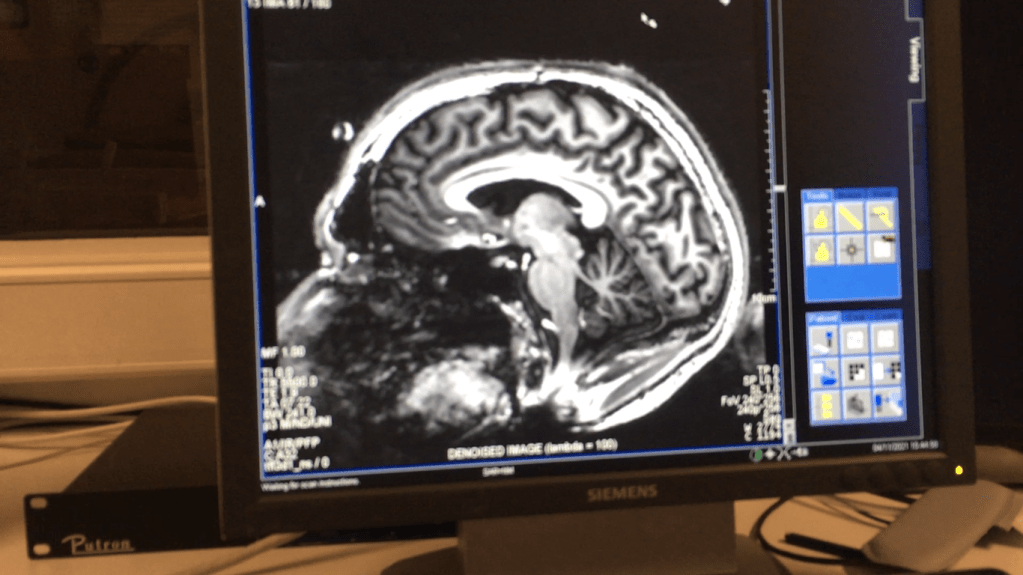

Pendant deux mois, je dois tous les jours bouger les doigts de mon membre fantôme afin de l’exercer, un IRM fonctionnel est réalisé avant et après l’entraînement de deux mois afin d’observer si les zones du cerveau correspondant au membre fantôme peuvent évoluer (en attente des résultats).